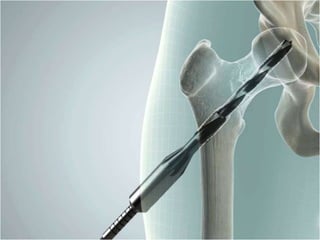

Get your (femoral) head fixed right

•   60% larger frontal load area

•   Strong, secure fixation

•   Rotationally stable

•   One shot (centre-centre) fixation

•   Dynamic sliding compression

•   Reversible & removable

X-BOLT®

Dynamic Hip Plating

Surgical Technique